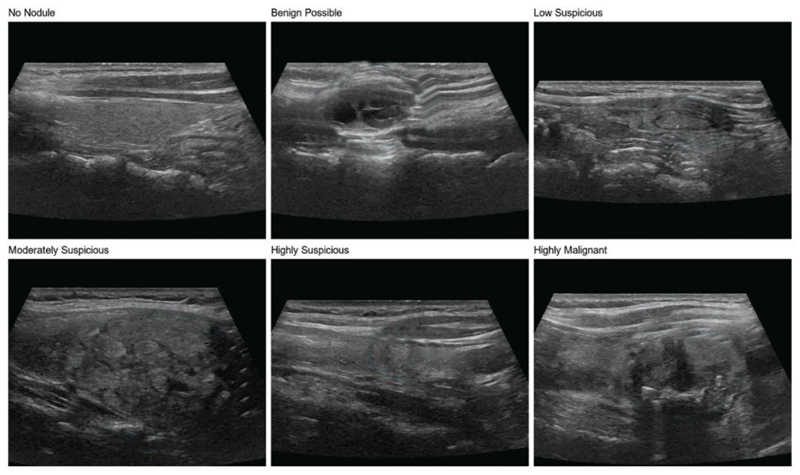

Methods: A novel method, ThyroidNet, is introduced and evaluated based on deep learning for the localization and classification of thyroid nodules. First, we propose the multitask TransUnet, which combines the TransUnet encoder and decoder with multitask learning. Second, we propose the DualLoss function, tailored to the thyroid nodule localization and classification tasks. It balances the learning of the localization and classification tasks to help improve the model's generalization ability. Third, we introduce strategies for augmenting the data. Finally, we submit a novel deep learning model, ThyroidNet, to accurately detect thyroid nodules.